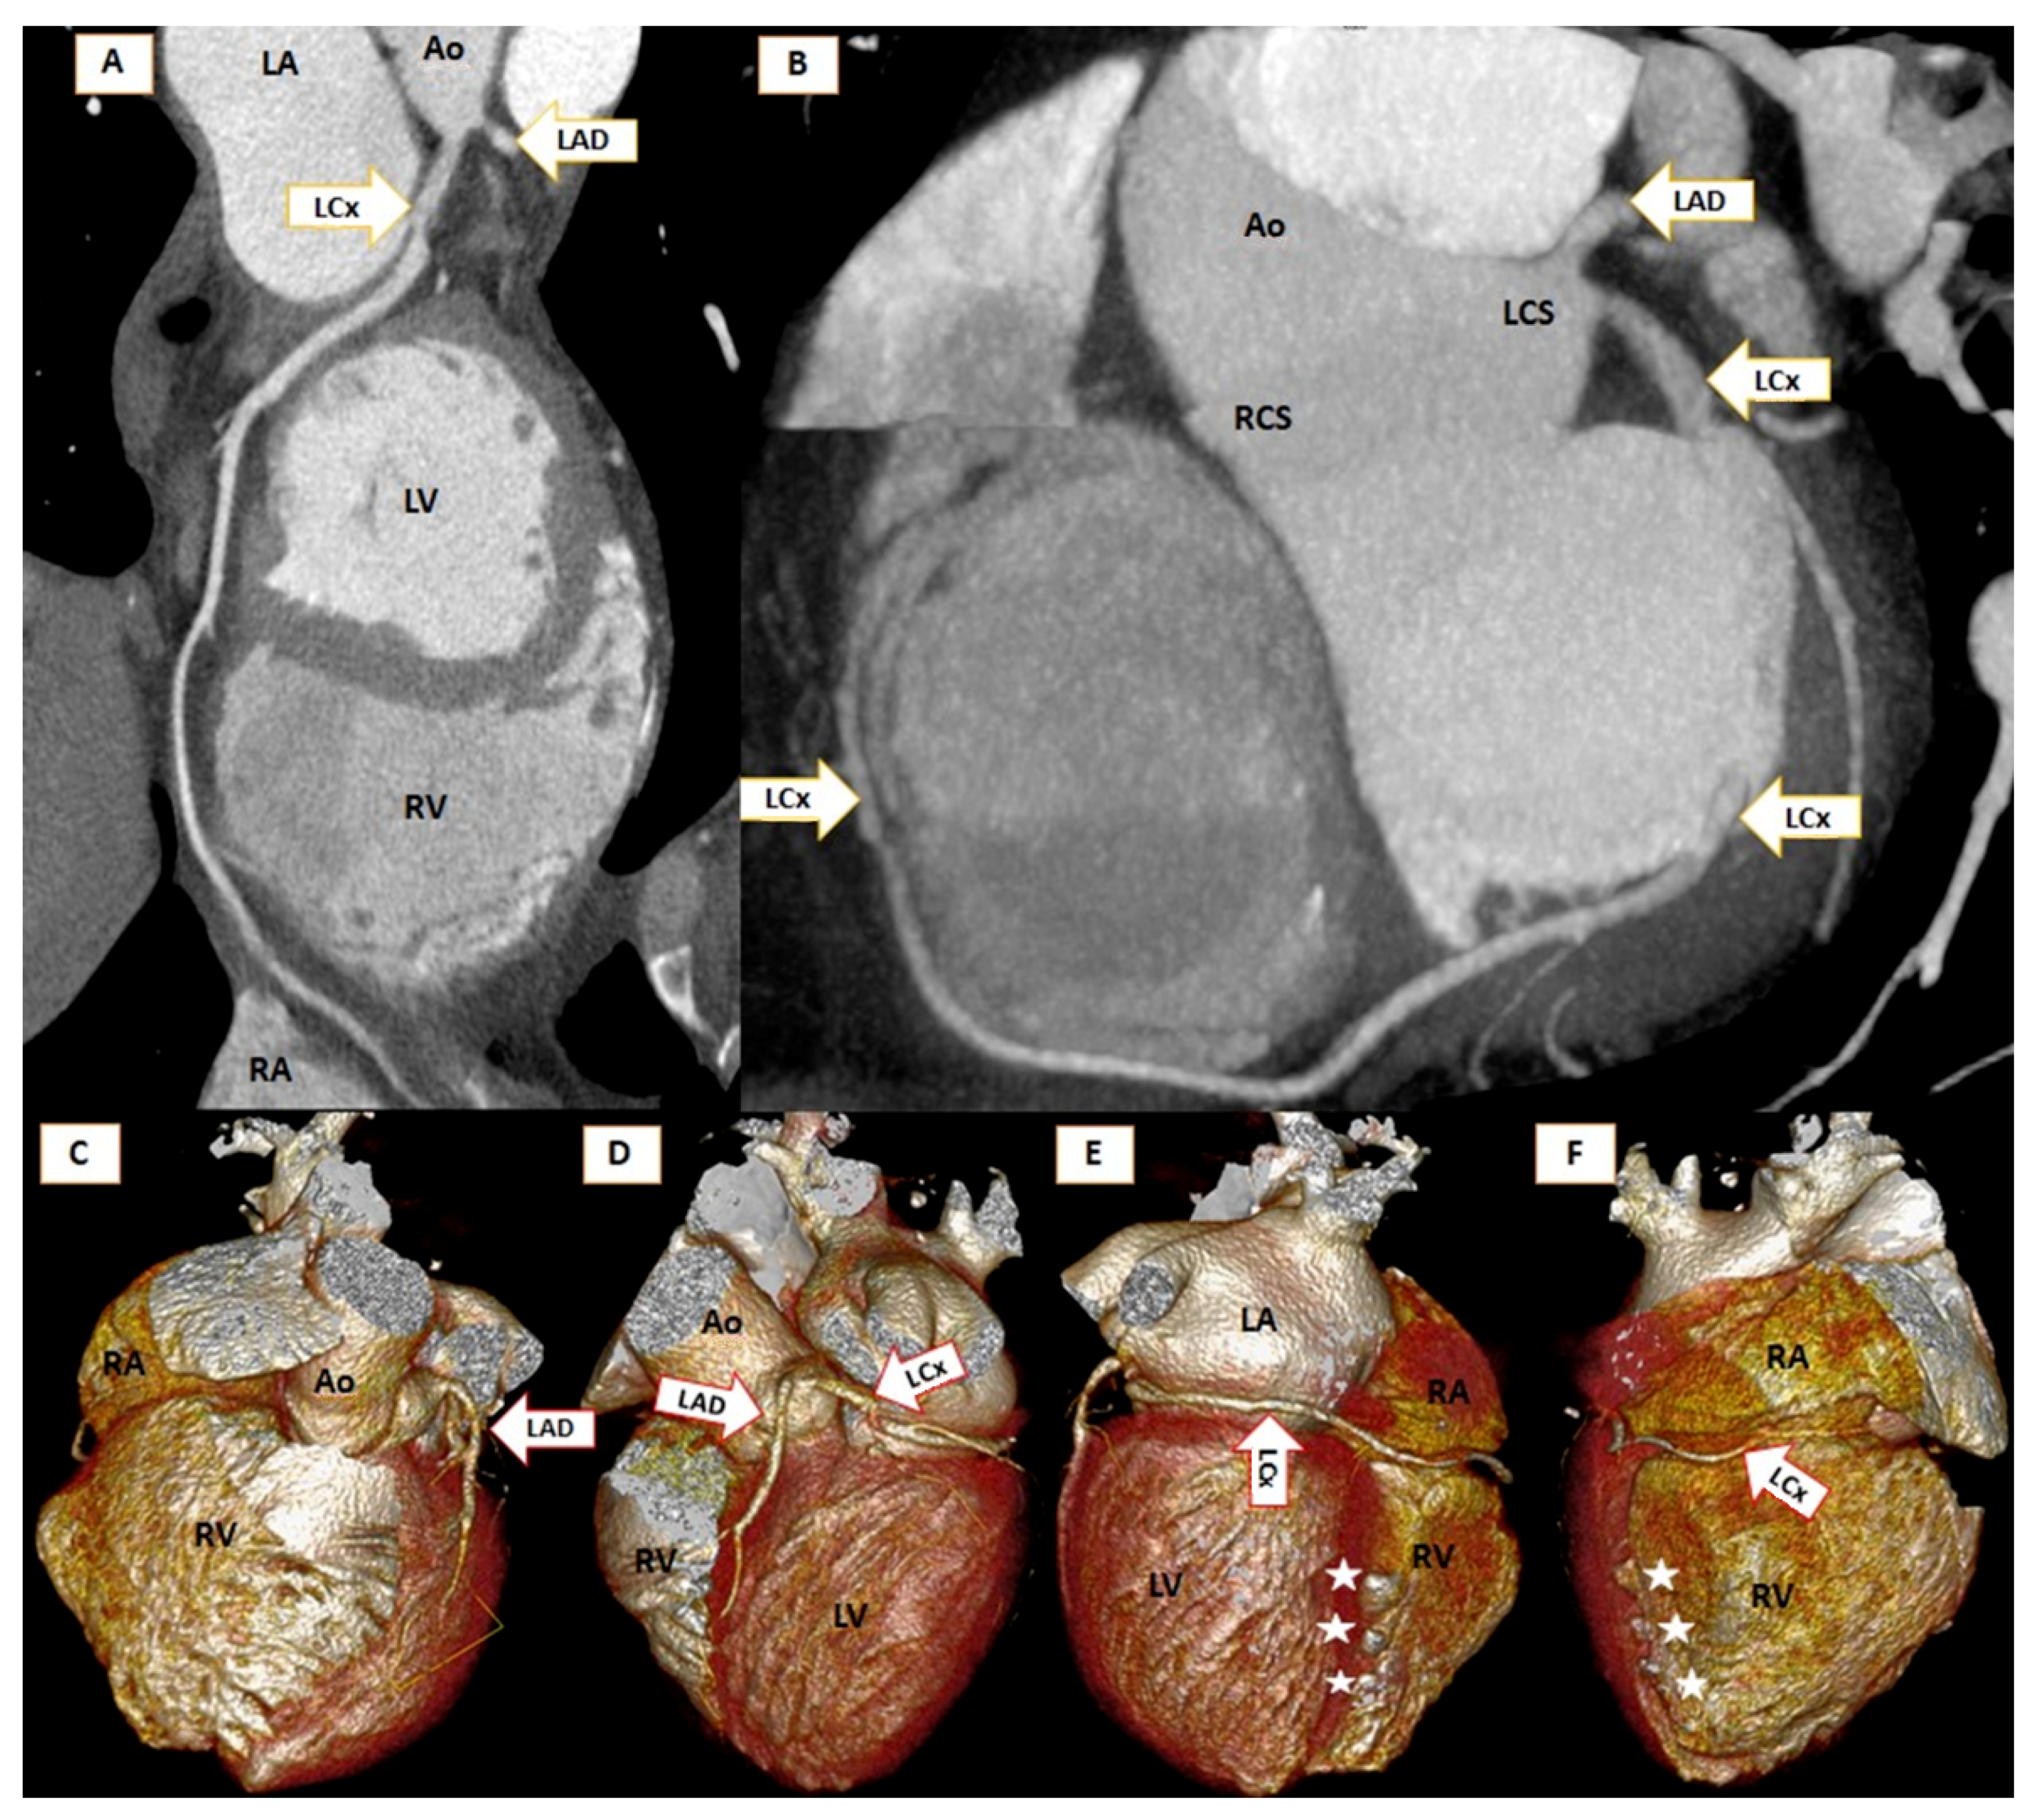

Absence of Both Right and Left Main Coronary in a COVID Survivor